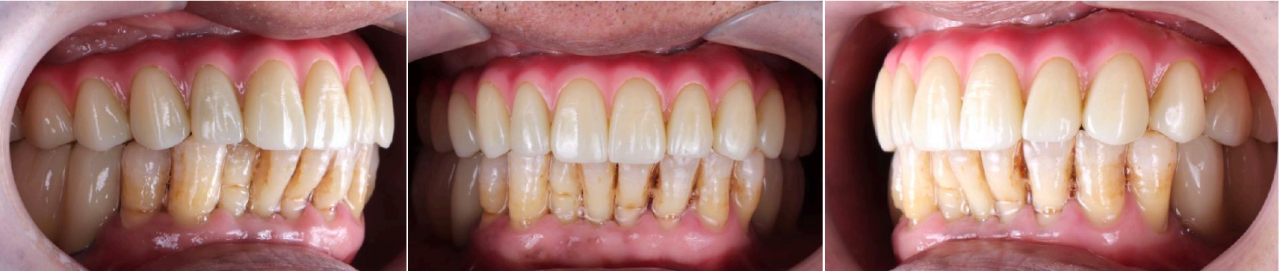

口外检查:面部对称无偏斜,面下1/3垂直高度正常,口角无偏斜,鼻唇沟加深,中线略偏右侧。低位笑线,前牙开唇露齿。开口度正常范围。

口内检查:13-23牙龈退缩,牙齿松动2-3度,14-17,24-27缺失,牙龈颜色质地正常。36,37,45,46,47缺失,下颌余留牙松动1-2度。

牙周刮治后两周复查